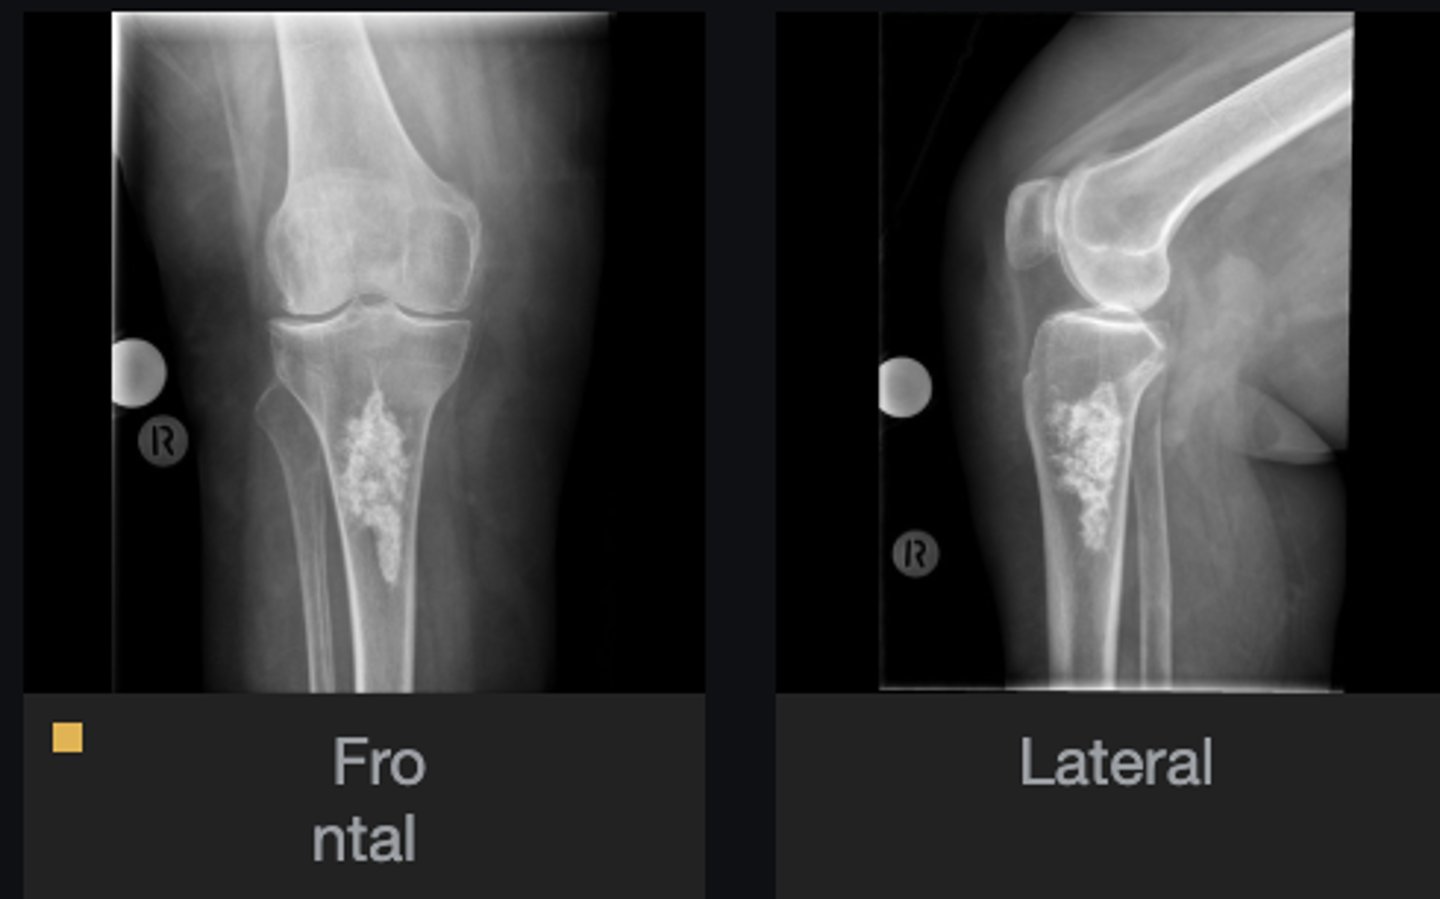

Lateral proximal tibia

Bone

<p>Bone</p>

- Longitudinal: epiphysis/metaphysis (up to joint surface)

- Eccentricity: eccentric

- Transverse: medullary

Location

- Lytic

- Geographic

- Short zone of transition

Behavior

<p>Behavior</p>

Giant cell tumor

Most likely diagnosis?

<p>Most likely diagnosis?</p>

Refer to orthopedist or oncologist

Next step?

<p>Next step?</p>

Could be aggressive (20%)

Concerns/complications?

<p>Concerns/complications?</p>